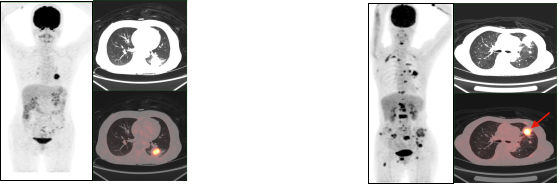

1.2放疗前确定肿瘤病灶生物靶区,提高放疗疗效

肺癌放疗前确定生物靶区:左肺下叶鳞癌患者(右图所示),左下肺癌病灶并远端阻塞性肺不张,PET/CT可以准确区分肿瘤组织与非肿瘤组织,确定肿瘤病灶生物靶区。

1.3早期发现和检出肿瘤,鉴别肿瘤良恶性

早期肺癌发现及鉴别:PET/CT显像示左肺上叶前段软组织灶(左图所示),糖代谢明显增高(SUVmax=15.3),经手术病理证实为肺腺癌。